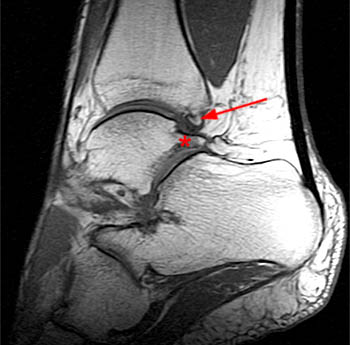

| A sagittal T1-weighted image demonstrates a large os trigonum (asterisk). T2-weighted imaging (not shown) demonstrated mild edema and cyst formation within the adjacent talus. |